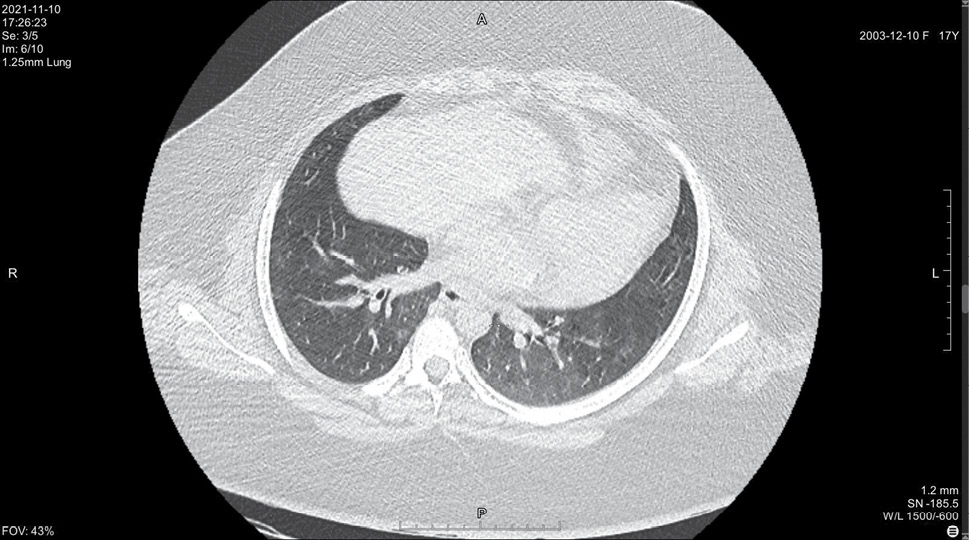

На 14 день болезни (10.11, 7 день госпитализации) была выполнена спиральная компьютерная томография грудной клетки, где выявлены признаки двусторонней интерстициальной полисегментарной пневмонии (рис. 1–8). Форма грудной клетки описана как обычная. Легочные поля расправлены. На томограммах бронхиальное дерево визуализировано до субсегментов: сами бронхи не деформированы, их просвет в пределах нормы, устья свободны, проходимость сохранена на всем протяжении. Во всех сегментах с обоих сторон определялись полиморфные, сливные участки уплотнения легочной ткани по типу матового стекла с участками консолидации. На этом фоне были видны просветы бронхов. Определялись фиброзные тяжи в проекции апикальной плевры обоих легких. Контуры диафрагмы четкие, синусы свободные, свободная жидкость в плевральной полости отсутствовала. Трахея обычной формы и размеров, карина острая. Сосудистые структуры верхнего средостения с четкими контурами и нормального диаметра, стенки сосудов без кальцинатов. Медиастинальные лимфоузлы и лимфоузлы корней обоих легких (без контрастного усиления) визуализированы единично, не увеличены. Сердце расположено обычно, размеры в пределах нормы. Выявлены умеренные дегенеративно-дистрофические изменения грудного отдела позвоночника. Мягкие ткани грудной клетки без особенностей. По заключению врача-рентгенолога, объем пораженной легочной паренхимы достигал 95%. Наиболее вероятно, что патологический процесс у пациентки имел вирусную природу.

Рисунок 1. Томограмма легких на уровне ThIII

Рисунок 2. Томограмма легких на уровне ThIV

Рисунок 3. Томограмма легких на уровне ThV

Рисунок 4. Томограмма легких на уровне ThVI